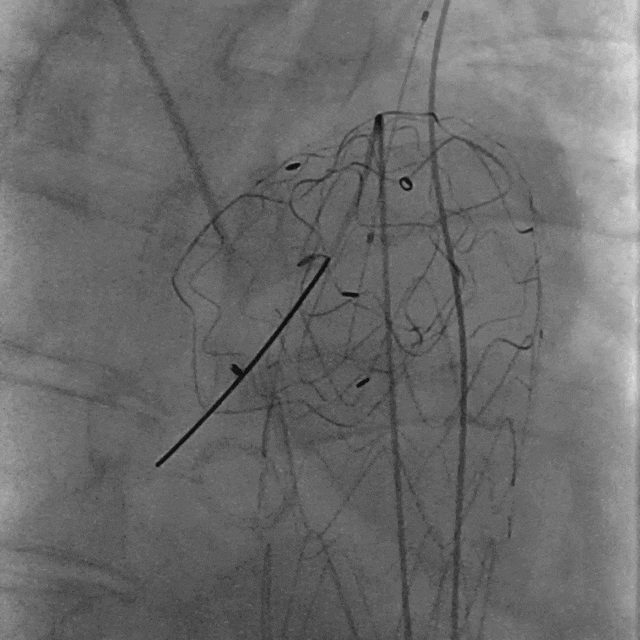

04. 引入9mm球囊扩张支架,于开窗处精准释放扩张。

泥鳅导丝怎么用曲乐丰教授团队:0.018"和0.035"普通泥鳅导丝行胸主动脉弓上分支原位开窗的病例分享_https://www.jmylbn.com_新闻资讯_第39张

置入9mm球囊扩张支架

泥鳅导丝怎么用曲乐丰教授团队:0.018"和0.035"普通泥鳅导丝行胸主动脉弓上分支原位开窗的病例分享_https://www.jmylbn.com_新闻资讯_第40张

球扩分支支架

05. 复查造影提示主动脉溃疡隔绝完全,无内漏,左锁骨下动脉血流通畅。

泥鳅导丝怎么用曲乐丰教授团队:0.018"和0.035"普通泥鳅导丝行胸主动脉弓上分支原位开窗的病例分享_https://www.jmylbn.com_新闻资讯_第41张

LSA造影

泥鳅导丝怎么用曲乐丰教授团队:0.018"和0.035"普通泥鳅导丝行胸主动脉弓上分支原位开窗的病例分享_https://www.jmylbn.com_新闻资讯_第42张

升主动脉造影